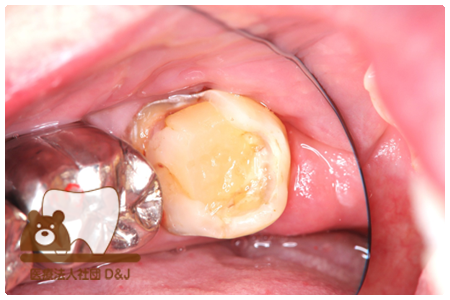

症例4フルジルコニアクラウン 左下6

治療前

治療後

37歳 男性

- 治療内容

- 以前のクラウンがセメントの劣化により外れた為その上にフルジルコニア製の被せ物を装着しました。見た目と強度を両立した自由診療の治療です。

- 治療期間

- 1カ月

- 費用

- 自費

フルジルコニアクラウン:77,000円(税込)

(R8.1月時点)

- その他の治療の費用は含まれておりません。

- リスク・副作用

- 硬い素材のため、かみ合う歯に負担がかかることがあります。将来取り外す場合に歯に負担がかかることがあります。強い力が加わると、まれに欠けたり割れたりすることがあります。